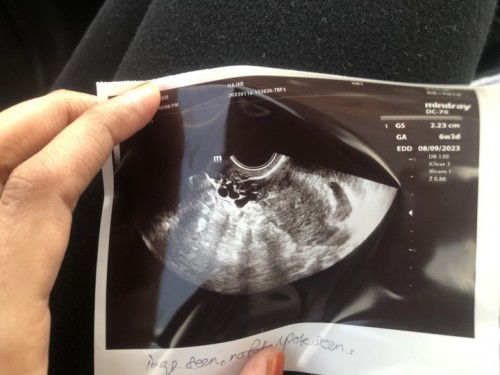

6week kantung kosong by TVS , kantung xnampak bulat

Hei mommy , sewaktu 4week scan saiz kntung 0.52 cm , now 6week seperti d gamba .. emm normal ke kantung xbulat eyhh … risauu hmm Kantung d sebelah kiri . Sebelah kanan ialah kilang telur. Normal ke first scan kantung d sebelah kanan , td scan doktor lain kantung tu sebelah kanan pulak .